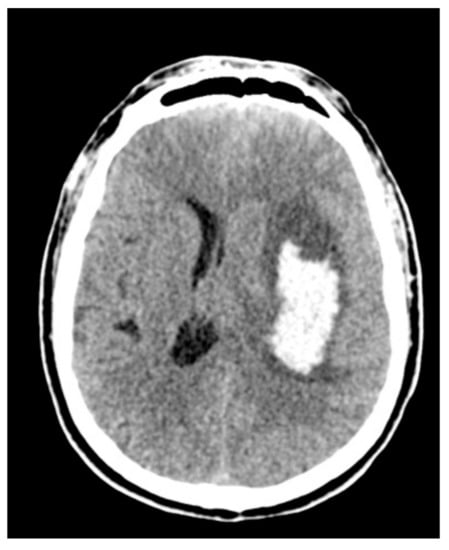

2.6. Surgical Management

Figure 4. Control computed tomography (CT) after the microscopic minimally invasive subtotal evacuation of the clot.